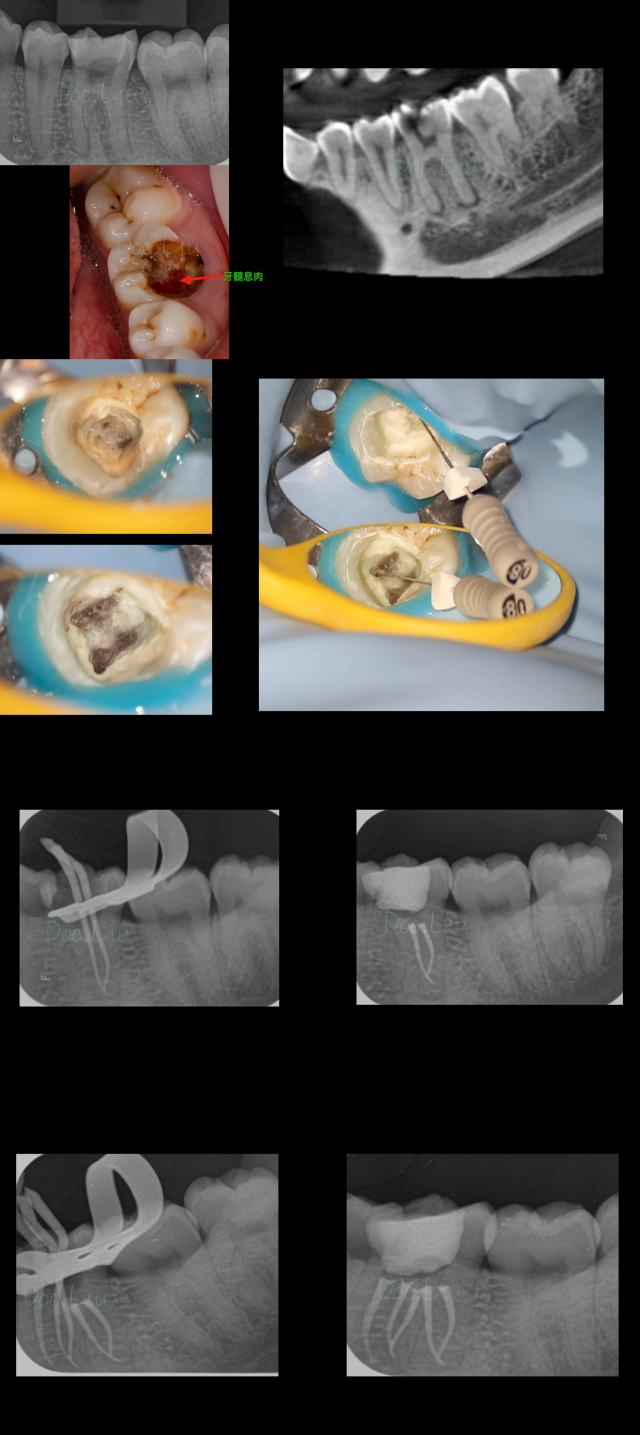

【病例展示

病例一

病例二

病例三